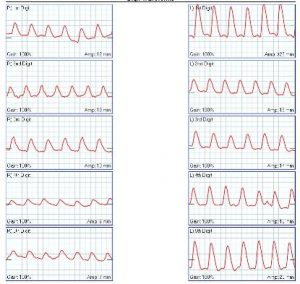

- Is there normal blood flow to the toes? Look at the tracing below. They are from a study called photoplethysmography (or PPG). They are normal. It is hard to have blocked arteries and normal blood flow, wouldn’t you say?

- What tests will my doctor order? Your doctor will probably run a few types of tests. They may want to test blood flow to the toes. They can do that with the Ankle Brachial Index and with PPG’s. Also, they may look for the source of the problem. This is done with blood tests and with ultrasound. The ultrasound can be of the heart or of the arteries.